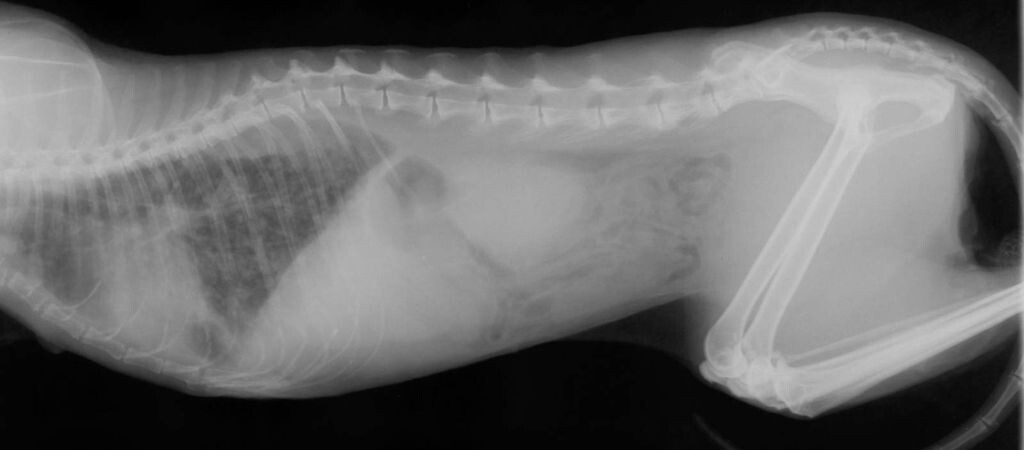

Я прослушала легкие Мурки и сразу заметила нехарактерные хрипы в нижних долях. Это не было похоже на обычный комок шерсти или легкую простуду. Я предложила сделать рентген, чтобы исключить серьезные патологии. Когда я обернулась, чтобы посмотреть на то, получился ли снимок, то картина сразу стала ясной: там были затемнения в легких, характерные для пневмонии. Вот даже на расстоянии в пару метров они были видны.

Смотреть на легкие - они находятся слева, чернота - легикие, а серый фон - признаки пневмонии